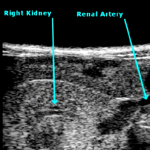

The OSR Mouse Clinic (OMC) stems from the above rationale and is the follow-up and consolidation of a Regione Lombardia-funded project (EMDM), which aimed at the establishment and implementation of a large, dedicated facility (the European Mouse Disease Models Center) whose goal is the development and functional assessment of mouse disease models, both for the dissection of the underlying pathogenic mechanisms and for the screening and validation of innovative diagnostic and therapeutic procedures. OMC has been conceived to face the challenges posed by the development of mouse models of disease that are more reliable and display higher predictive value for the corresponding human condition. OMC has developed and standardized a coordinate set of activities, including the creation of a non invasive imaging facility, based on the acquisition of dedicated equipment (7-Tesla small bore MRI; micro-CT scanner; micro-US scanner; optical imaging scanner; micro-PET), the creation of a comparative pathology Unit and the implementation of a dedicated area for the use of mouse pathogens. OMC also aims at potentiating the existing Conditional Mutagenesis Facility by implementing novel approaches to attain tissue-, stage- and site-specific transgene expression in mouse mutant strains, mainly through lentiviral vector-mediated transduction of blastocysts.